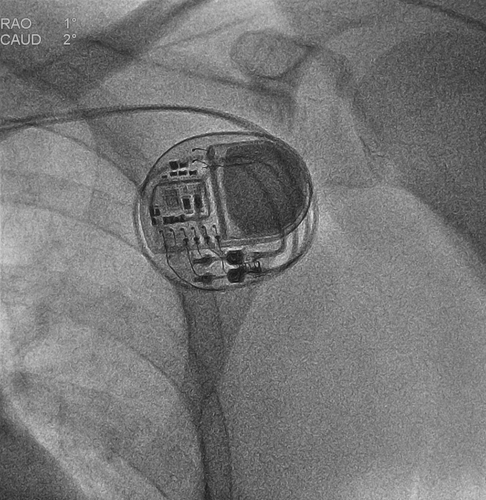

La surveillance systématique du rythme cardiaque peut conduire à une détection plus précoce de la FA. Les dispositifs cardiaques implantés permettent la surveillance continue du rythme cardiaque et peuvent enregistrer de courts épisodes d'arythmies auriculaires au moyen de capteurs intracardiaques ou sous-cutanés, appelés FA infra-clinique ou épisodes auriculaires à fréquence élevée (Atrial High Rate Episodes, AHRE).

Les AHRE éligibles pouvaient avoir été enregistrés par un stimulateur cardiaque, un défibrillateur, un dispositif de resynchronisation ou un enregistreur en boucle implanté doté de capacités de surveillance du rythme. L'âge moyen était de 78 ans, 37,4 % étaient des femmes, la durée médiane des AHRE était de 2,8 heures, le nombre médian d’AHRE était de 2,8 dans chaque groupe, la médiane du score CHA2DS2-VASc (utilisé pour prédire le risque d'AVC ischémique chez les patients atteints de FA, il varie de 0 à 9, des scores plus élevés indiquant un risque plus élevé) était de 4. Le critère de jugement principal en matière d'efficacité était un critère composite de décès d'origine cardiovasculaire, d'AVC ou d'embolie systémique. Le résultat en matière de sécurité était un composite de décès quelle qu'en soit la cause ou d'hémorragie majeure.